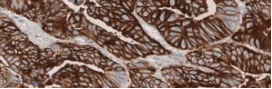

Studies have evaluated both membranous staining and percentage of tumour cells stained for CLDN18.2 expression.1,2

In G/GEJ tumours, CLDN18.2 is reported as the percentage of tumour cells stained with moderate-to-strong membranous stain intensity.1

• Tissue slides with tumour cells present can demonstrate varying levels of CLDN18 membranous staining intensity, ranging from no staining to strong staining (0 to 3+)

• Many studies have included percentage of tumour cells with only moderate-to-strong (2+/3+) membranous staining for scoring CLDN18

When reporting CLDN18.2 expression, both staining intensity and percentage of tumour cells stained should be included.1